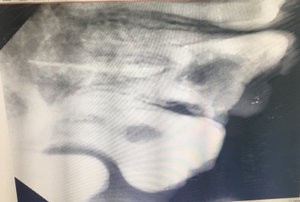

После удаления нерва из зуба, кажется четырнадцатый, на верхней челюсти, проткнули на 2 сантиметра дальше корня, я показался другому врачу и он говорит, что теперь нужно удалять зуб.

Неужели ничего нельзя поделать, чтобы сохранить зуб? Чем-то запломбировать этот канал? Мне 66 лет, их, зубов, уже почти не осталось.

В принципе, доктор прав, также возможно провести хирургическую манипуляцию (резекция верхушки корня).